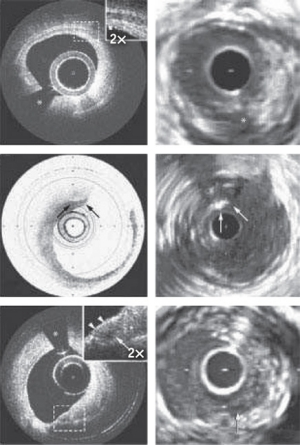

Even though OCT cannot image as deeply as ultrasound, CT or MRI (its penetration depth in tissue is just 2−3 mm), it has advantages over these techniques. The operation of OCT is similar to that of ultrasound imaging (it uses low-coherence light the way ultrasound uses sound waves), but it produces images of superior resolution (see Fig. 1). And it does so without contact—which is a key advantage for applications such as ophthalmology.

In the medical imaging world, OCT, with resolution of 5−10 μm, sits between ultrasound and microscopy. Ultrasound, with a resolution of around 150 μm, is best used to visualize organs, while confocal microscopy, with resolution of 1 μm, is best for imaging at the cellular level, though it has the disadvantage that the tissue must be excised first. OCT fits in nicely where high-resolution, noninvasive imaging of tissue morphology is required.

Almost from the start, the potential for using OCT in the evaluation of atherosclerosis, or thickening and hardening of the walls of medium and large arteries, was seen as a powerful application. Today, OCT is being marketed for vulnerable plaque assessment and stent visualization: In May 2010, LightLab Imaging, since acquired by global medical device company St. Jude Medical, Inc. (St. Paul, MN), announced receipt of the FDA's first clearance for a clinical OCT system to be applied to cardiovascular imaging (see Fig. 3). Competitor Volcano Corp. expects commercial release of its second-generation OCT catheter and system in Europe early this year and in the U.S. in mid-2011. Volcano plans to combine OCT and IVUS on the same catheter, and in fact has a roadmap to accomplish this.Other applications